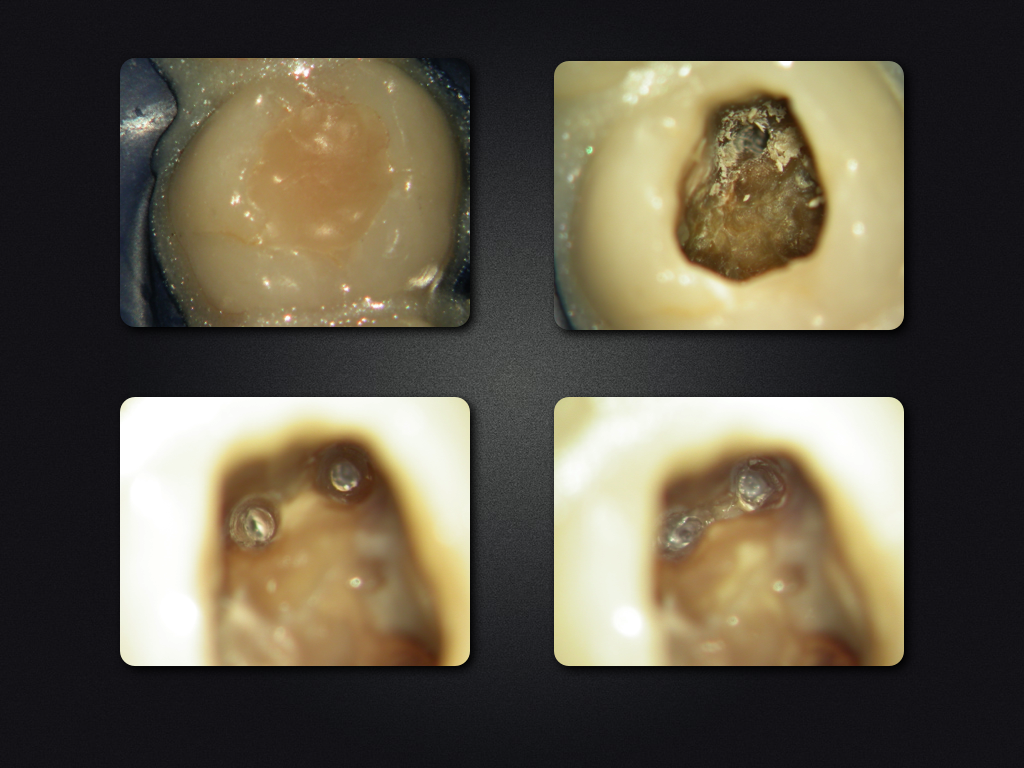

26D.006

2D vs. 3D (XXVI)